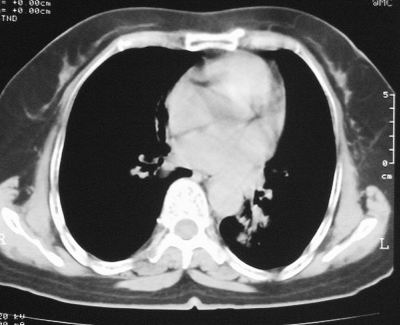

患者,女,64岁,4年前左腮腺"多形性"腺瘤手术治疗史.现复查胸部ct见左下肺块状影,该影与原左腮腺手术是否有联系?

本次复查胸部ct

左下肺软组织块影,有分叶、毛刺、空泡及胸膜牵拉征,左下肺周围性肺癌。

左肺下叶周围型肺癌,支持!(软组织肿块+分叶+毛刺+空泡+胸膜凹陷征)

左下肺软组织密度影,可见分叶,边缘可见毛刺征,胸膜增厚,强烈要求左下肺周围型肺癌

左下肺后基底段实性肿块,周围有毛刺,病变周围有肺气肿,与降主动脉间有条带状影相连,病灶4年前查体发现,纵隔内未见肿大淋巴结。考虑.肺隔离症,建议增强扫描与周围型肺癌鉴别。